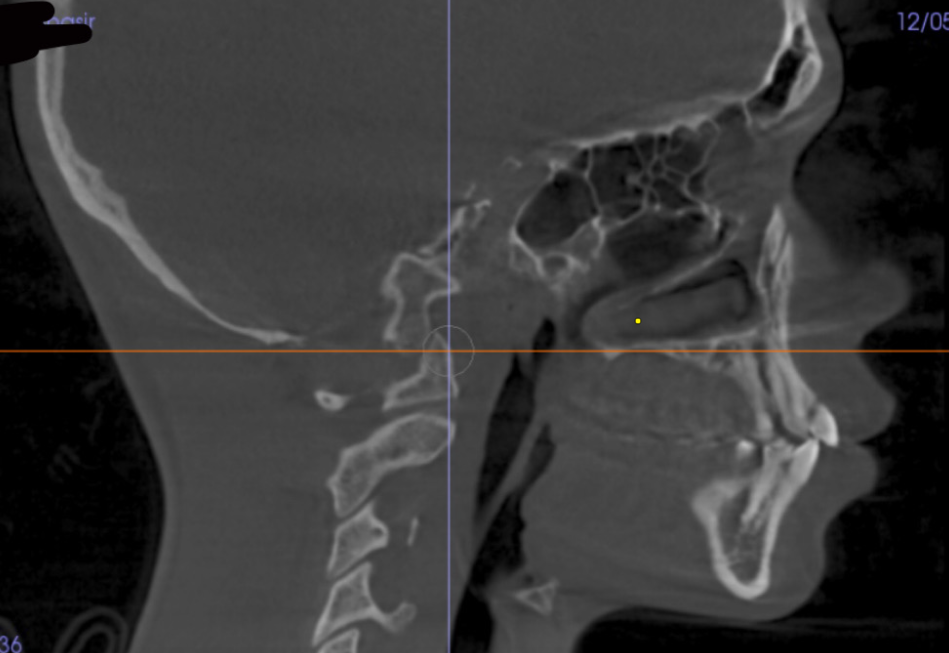

Went to the orthodontist the other day and got these scans. I’m trying to figure out what I should change or improve to look better. Based on this, what do you think needs work and what can I do to improve it?